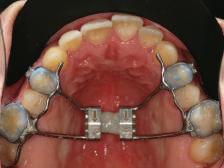

орални снимки и снимки на позата, пал пация на мускулите, брукс-чекър, оклу зограми, кондилография, рентгеногра фии, СВСТ и ядрено-магнитен резонанс на темпоромандибуларните стави). Преди началото на ортодонтското лечение всички стари възстановява ния бяха свалени и бяха заменени с дъл госрочни временни от хибридна керами ка. На девитализираните зъби бе прове дено ендодонтско релечение. Индивиду ализиран оклузален сплинт бе направен с цел да се постигне контролирано репо зициониране на долната челюст, като носенето му продължи три месеца до възстановяване на правилната позиция на ставния диск и затихване на орофаци алната болка и дискомфорт в ставата. Брекетите в горната челюст бяха за лепени, за да започне подреждането и нивелирането на зъбите, докато паци ентът все още носеше сплинта. След края на терапията със сплинта бе на правена кондилография, за да се потвър ди триизмерната позиция на долната челюст. След залепване на брекетите в долна

та челюст 4 минивинта (TADs) бяха по ставени в максилата – 2 в небцето и 2 интрарадикуларно във фронта, с цел да се извърши интрузия на цялата зъбна дъга, да се коригира гингивалната усмивка и да се позволи провеждането на обратна на часовниковата стрелка авторо

8 Dental Tribune Bulgarian Edition / октомври 2022 г. По време на лечението Фиг. 21 Фиг. 25 Фиг. 30 Фиг. 31 Фиг. 34 Фиг. 38 Фиг. 40 Фиг. 44 Фиг. 48 Фиг. 50 Фиг. 49 Фиг. 46 Фиг. 39 Фиг. 41 Фиг. 45 Фиг. 47 Фиг. 42 Фиг. 43 Фиг. 35 Фиг. 36 Фиг. 37 Фиг. 32 Фиг. 33 Фиг. 26 Фиг. 28 Фиг. 29 Фиг. 27 Фиг. 22 Фиг. 23 Фиг. 24